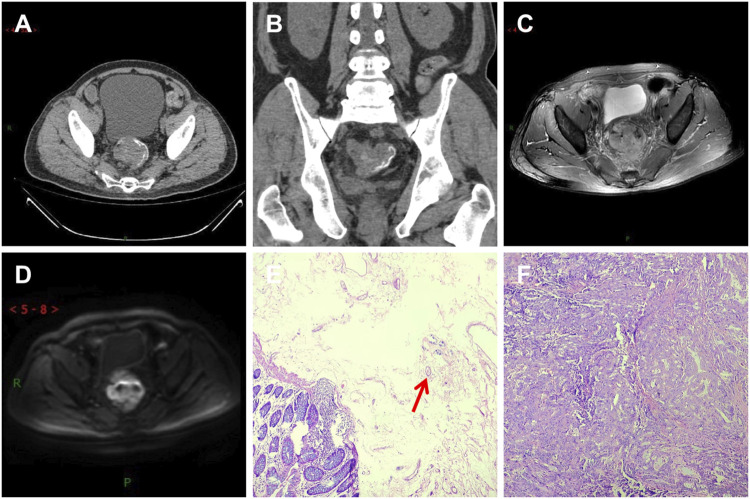

本研究旨在检查和比较有血吸虫病和无血吸虫病结直肠癌(CRC)患者的临床、放射学和病理学数据,并揭示伴有血吸虫病的结直肠癌的独特特征。这项回顾性研究基于从 341 名手术后和病理诊断为 CRC 的患者收集的数据。其中,101 名患者(A 组)被诊断为合并血吸虫病的结直肠癌(CRC-S),240 名患者(B 组)被诊断为未合并血吸虫病的结直肠癌(CRC-NS)。两组患者的临床数据、基于影像学的 TNM 分期、淋巴结转移、神经侵犯、血管癌栓和组织病理学分化情况进行了比较和分析。通过卡方检验发现,CRC-S(A 组)和 CRC-NS(B 组)患者的性别分布存在显著差异,P 值为 0.043,χ2 = 4.115。两组间 TNM 分期的总体分布存在差异(P = 0.034,χ2 = 6.764)。经配对比较,T3 期的差异有统计学意义(P = 0.005,χ2 = 10.626)。经过配对比较,分化良好的腺癌与中度和分化不良的腺癌之间的差异有统计学意义(p p > 0.05)。在 101 例 CRC-S 患者中,87 例(86%)在 CT 成像中显示出线性钙化。CRC-S 患者以男性为主,肿瘤分期多为中期,肿瘤分化程度高,恶性程度低。CT 成像可帮助识别血吸虫沉积的肿块和线性钙化。核磁共振成像可早期明确TNM分期,确定是否存在淋巴结转移、神经和血管侵犯。

This study aims to examine and compare clinical, radiological, and pathological data between colorectal cancer (CRC) patients with and without schistosomiasis and uncover distinctive CRC characteristics when accompanied by schistosomiasis. This retrospective study is based on data collected from 341 patients diagnosed with CRC post-surgery and pathology. Of these patients, 101 (Group A) were diagnosed with colorectal cancer co-occurring with schistosomiasis (CRC-S), while 240 patients (Group B) were diagnosed with colorectal cancer without concurrent schistosomiasis (CRC-NS). Both groups were compared and analyzed based on their clinical data, imaging-based TNM staging, lymph node metastasis, nerve invasion, vascular cancer thrombus, and histopathological differentiation. A Chi-squared test revealed a significant difference in gender distribution between the patients with CRC-S (Group A) and CRC-NS (Group B), with a p -value of 0.043 and χ2 = 4.115. Specifically, a higher incidence rate was observed among males in Group A. There was a difference in the overall distribution of TNM staging between the two groups (p = 0.034, χ2 = 6.764). After pairwise comparison, a statistically significant difference was observed in the T3 stage (p <0.05). The proportion of the T3 stage in Group A was significantly higher than that in Group B, indicating certain advantages. There was a difference in postoperative histopathological grading between the two groups (p = 0.005, χ2 = 10.626). After pairwise comparison, a statistically significant difference was observed between the well-differentiated adenocarcinoma and the moderately and poorly differentiated adenocarcinoma (p <0.05), with a higher proportion of welldifferentiated patients in Group A compared to Group B. There was no significant difference in age, lymph node metastasis, nerve invasion, and vascular invasion between the two groups of patients (p > 0.05). Among the 101 patients with CRC-S, 87 (86%) showed linear calcification on CT imaging. Patients with CRC-S are mainly male, with tumor staging mostly in the middle stage, high tumor differentiation, and low malignancy. CT imaging can help identify the presence of lumps and linear calcification indicative of schistosome deposits. MRI can early clarify TNM staging and determine the presence of lymph node metastasis and nerve and vascular invasion.